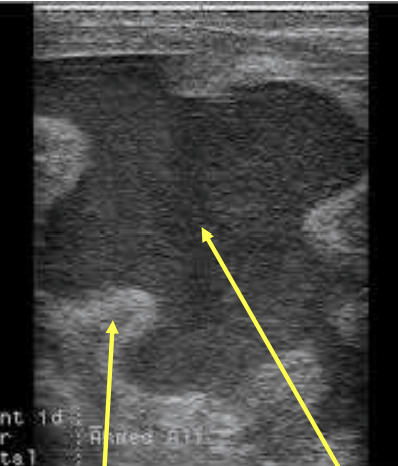

How does pyometra appear on ultrasound

thick uterine wall and hypoechoic fluid in the uterine lumen

How does pyometra look on ultrasound in dogs

uterine lumen is more anechoic because pus is more watery in dogs than other species